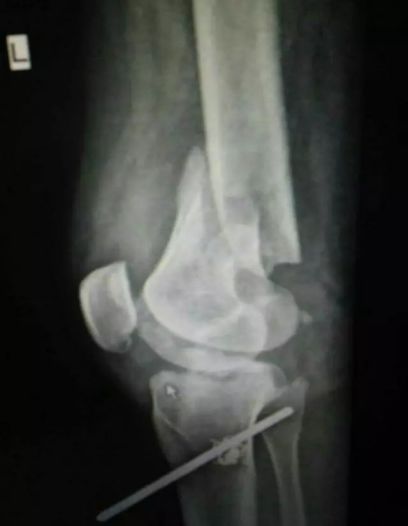

胫骨平台是位于胫骨上端的一个平台,与股骨的髁部形成膝关节。胫骨平台骨折是指胫骨平台部位发生的骨折,可能是由于直接撞击、跌倒或扭伤等原因引起。根据骨折的严重程度和位置,可分为多种类型,如单纯骨折、粉碎性骨折等。

并非所有胫骨平台骨折都适合保守治疗。以下情况可以考虑采用保守治疗:

无移位的胫骨平台骨折